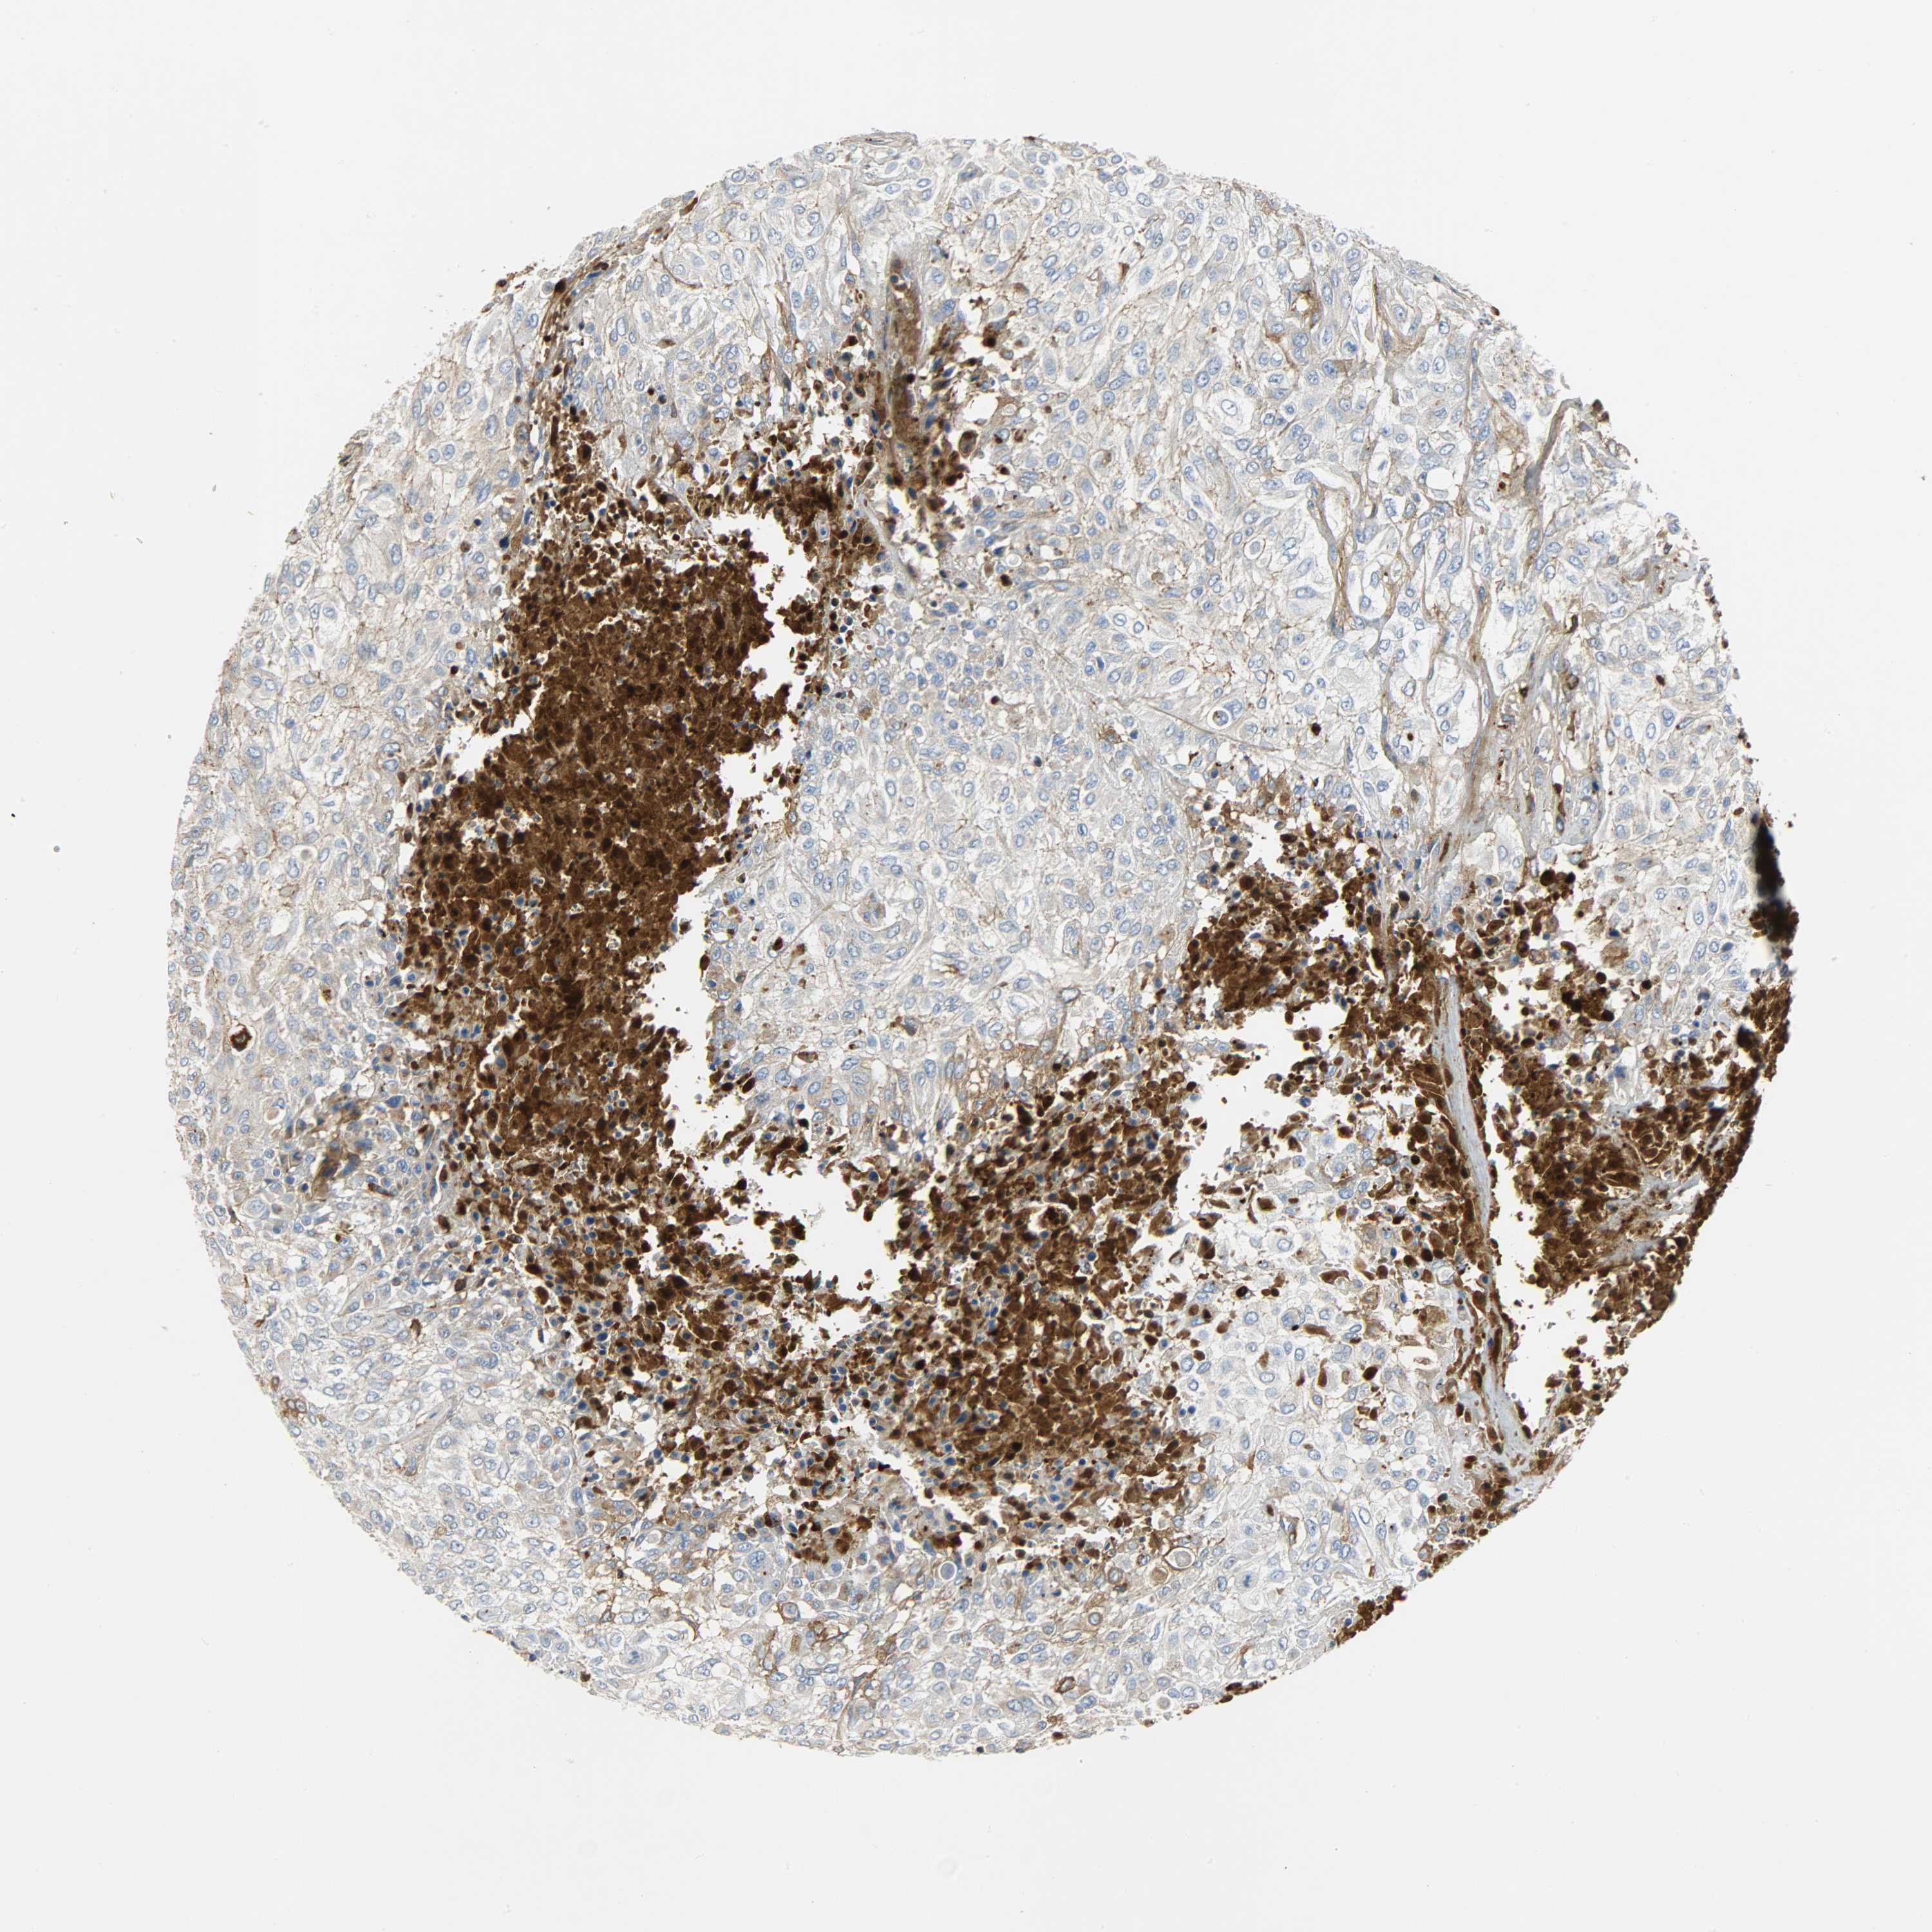

UROTHELIAL CANCER - Protein expressioni

A mouse-over function shows sample information and annotation data. Click on an image to view it in a full screen mode. Samples can be filtered based on level of antibody staining by selecting one or several of the following categories: high, medium, low and not detected. The assay and annotation is described here.

Note that samples used for immunohistochemistry by the Human Protein Atlas do not correspond to samples in the TCGA dataset.

Antibody stainingi

Antibody staining in the annotated cell types in the current human tissue is reported as not detected, low, medium, or high, based on conventional immunohistochemistry profiling in selected tissues. This score is based on the combination of the staining intensity and fraction of stained cells.

Each image is clickable and will lead to virtual microscopy that enables deeper exploration of all samples and also displays staining intensity scores, fraction scores and subcellular localization as well as patient and tissue information for each sample.

Antibody HPA027367

Antibody HPA027396

Antibody CAB005036

Staining

High

Medium

Low

Not detected

Intensity

Strong

Moderate

Weak

Negative

Quantity

>75%

75%-25%

<25%

None

Location

Nuclear

Cytoplasmic/membranous

Cytoplasmic/membranous,nuclear

Urothelial carcinoma, Low grade

Urothelial carcinoma, High grade